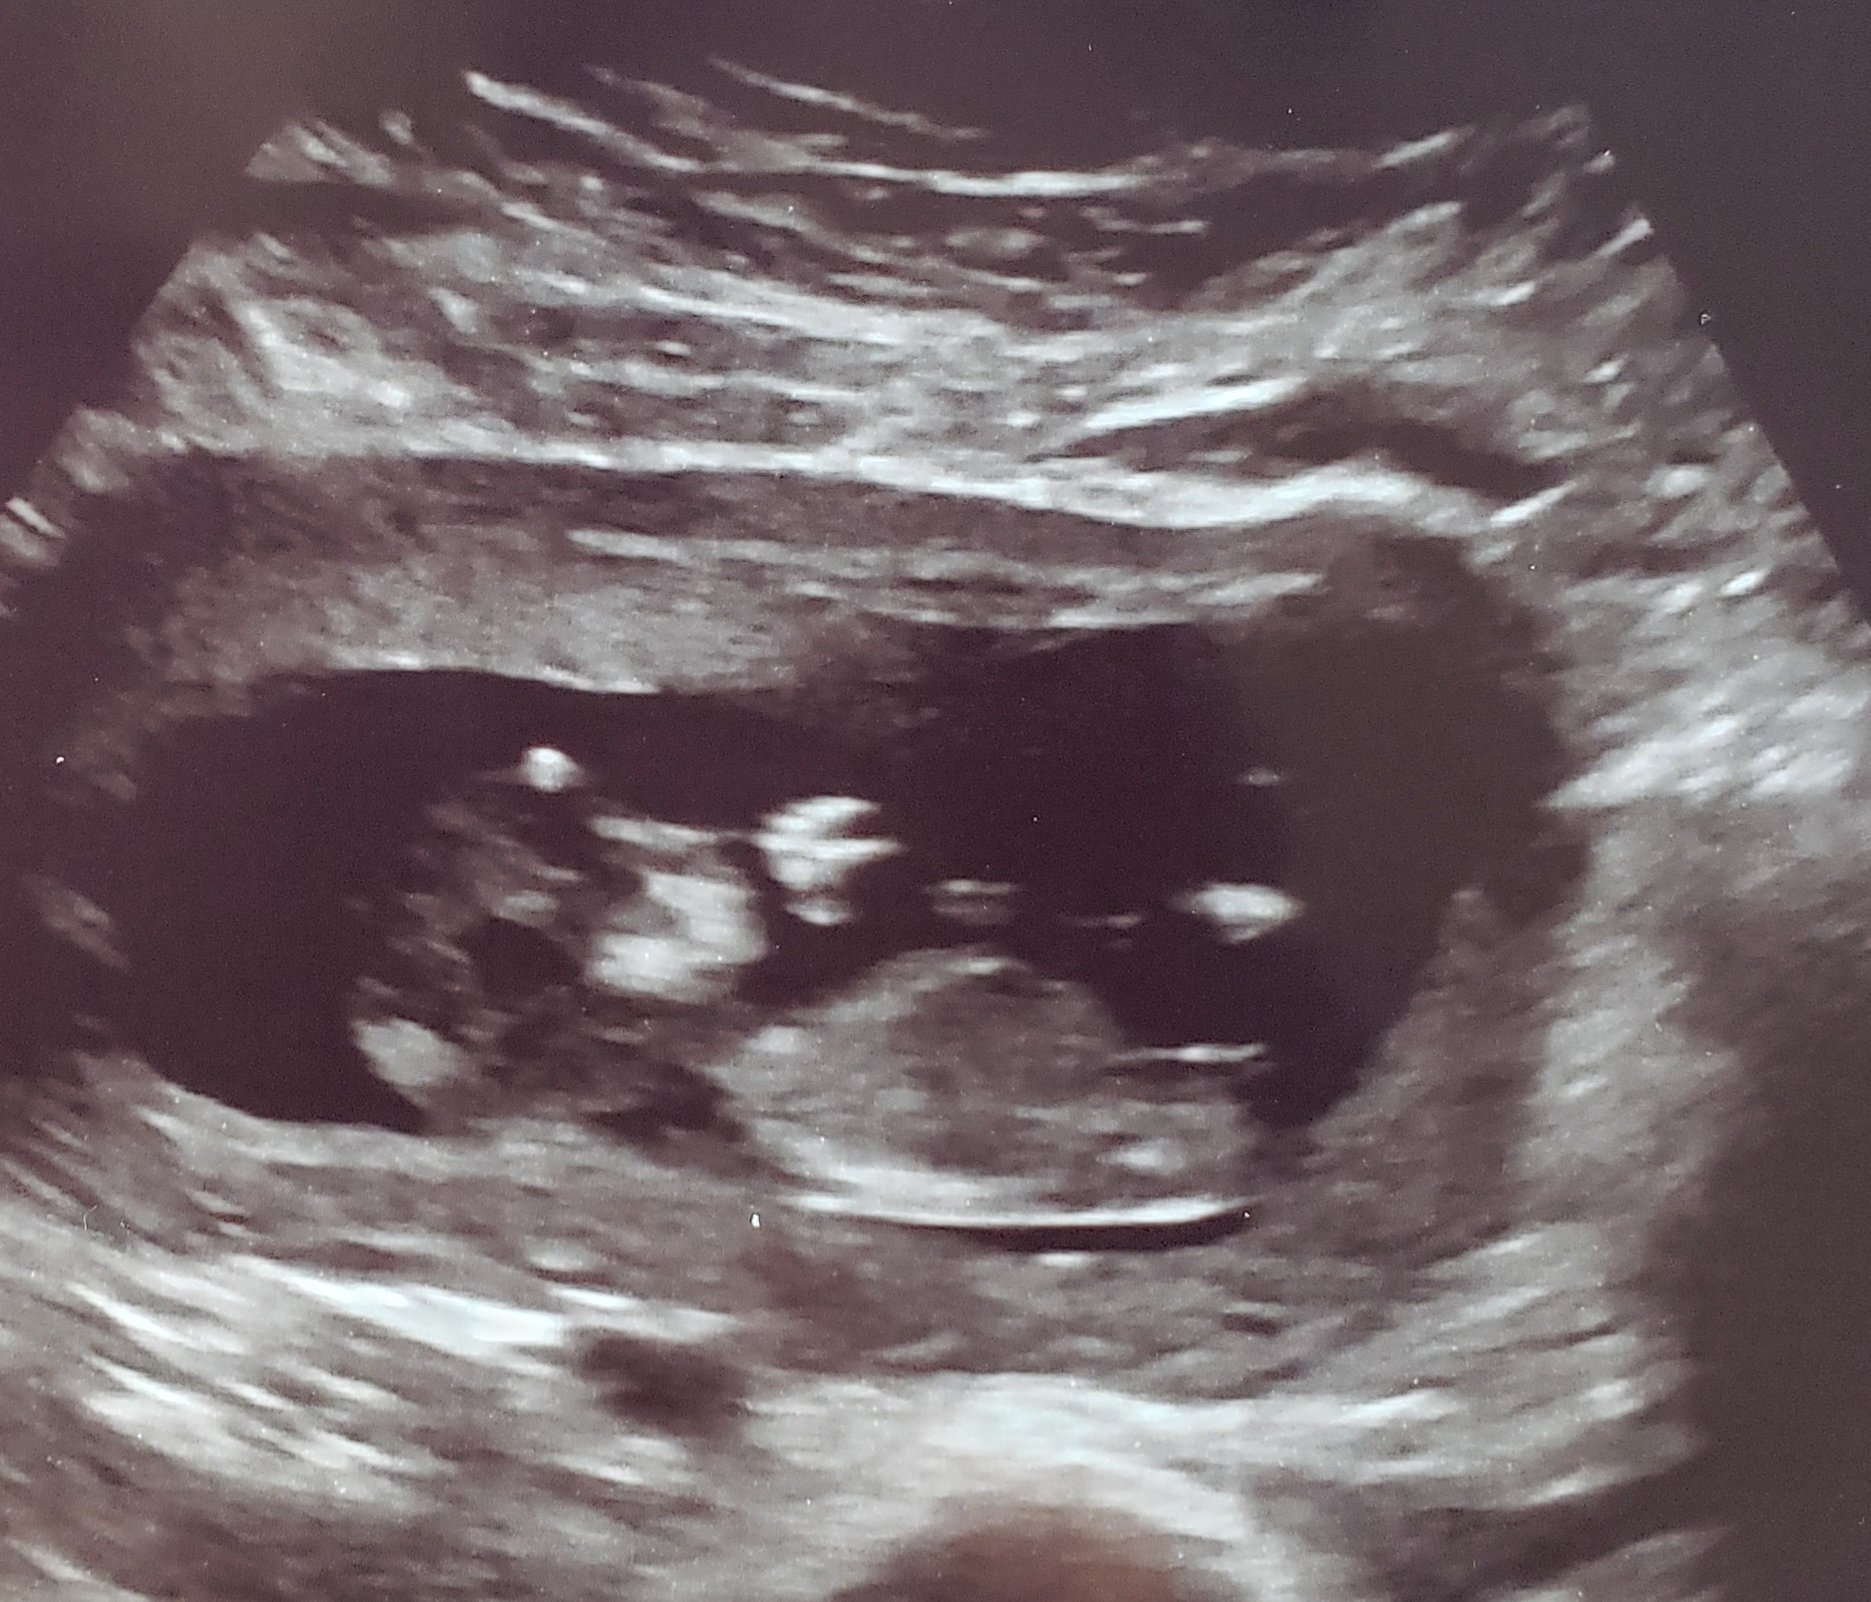

My ultrasound at 13 weeks when I went in for the NT scan! Had no idea that there are two in there !